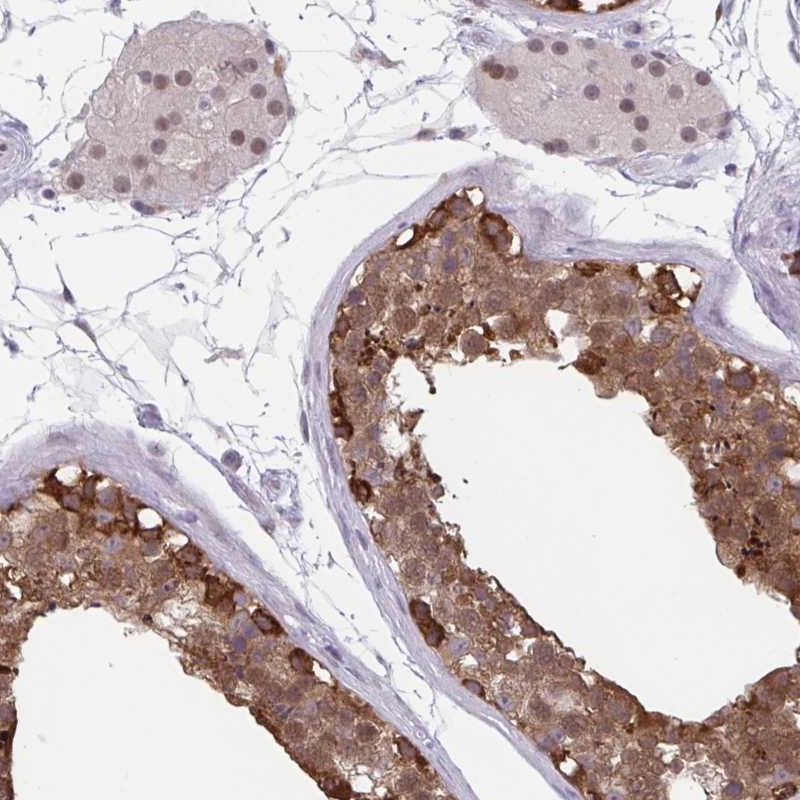

Immunohistochemical staining of human testis shows strong cytoplasmic and nuclear positivity in cells in seminiferus ducts, Leydig cells showed moderate nuclear staining.